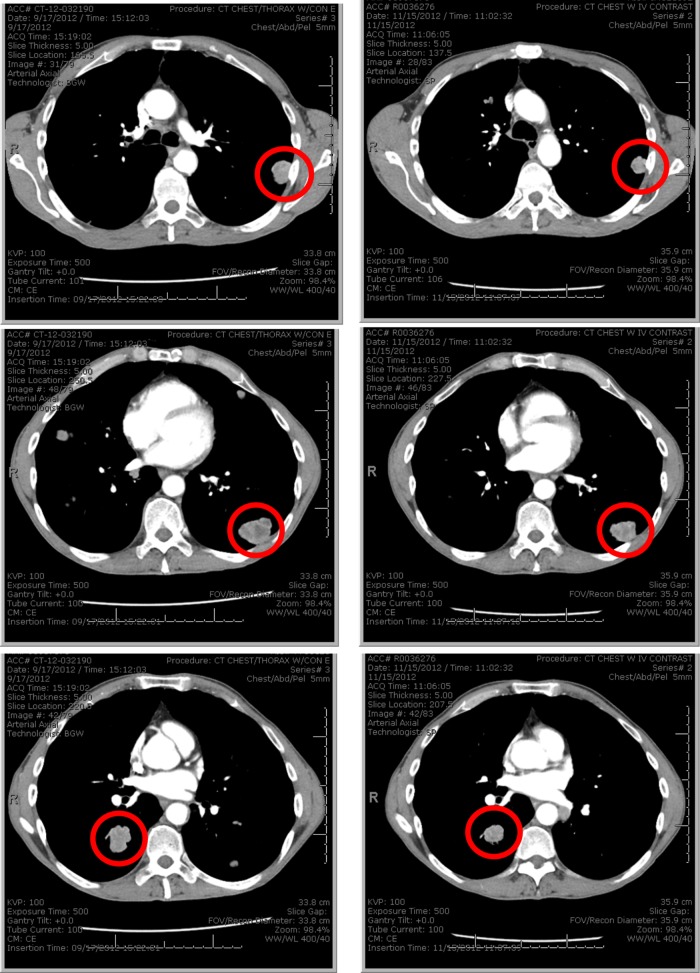

Of the 32 patients evaluable for radiographic response, the best response was stable disease in 12 patients (disease control rate 38%) and progressive disease in 20 patients. Radiographic responses and duration of therapy are shown according to tumour NQO1 status in Fig. 1a, b. Minor radiographic response was noted in 6 patients, including 1 patient with heavily pre-treated (five prior lines of therapy) metastatic bladder cancer (NQO1 H-score 200) treated at dose level 195 mg/m2 who experienced shrinkage of multiple pulmonary metastases (Fig. 2). After analysis of 20 patients with evaluable response and available NQO1 expression level, we observed a near significant association (P = 0.06) between tumour NQO1 expression (H-score ≥ 200) and response (Fig. 1c). Of note, no NQO1-negative (H-score 0) cases (N = 6) achieved disease control. Based on these observations, the protocol was amended to limit enrolment to NQO1-positive cases (H-score ≥ 200), following which an additional 8 patients were treated. PFS according to NQO1 level for the entire study population is shown in Fig. 1d. Four-month PFS rate was 26% in NQO1-high tumours vs. 13% in NQO1-low tumours (P = 0.3).

Fig. 2.

Example of minor radiographic response from ARQ 761. Patient had heavily pre-treated bladder cancer (five prior lines of therapy). Images show multiple pulmonary metastases that decreased in size after initiation of study treatment